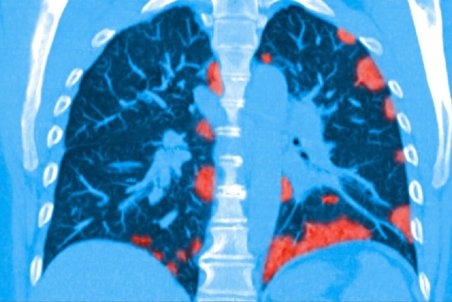

فیبروز ریوی چیست؟

فیبروز ریوی (Pulmonary Fibrosis) یک بیماری، پیشرونده، مخرب و ناتوانکننده ریه است که با ایجاد زخم در ریهها خود را نشان میدهد و با ترجمه تحتاللفظی "زخم ریهها" توصیف مناسبی است برای صدمهای که به ریهها وارد و اختلالی که در تنفس ایجاد میکند.

فیبروز ریوی چیست و چگونه درمان میشود؟

فیبروز ریوی، سفت شدن و ضخیم شدن بافت ریه است که با نفستنگی، خفگی ریهها و احساس کمبود اکسیژن همراه است. این بیماری عملکرد ریه را مختل میکند و زخمهای ناشی از آن معمولاً درمانی ندارند!